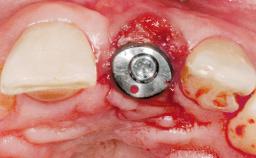

Late Placement of an Implant in a Maxillary Left Central Incisor Site

A 36-year-old female patient was referred for the replacement of the upper left central incisor (tooth 21), which had fractured. Although the tooth had been asymptomatic for many years, the crown began to loosen, at which time she presented to her dentist for an assessment. Teeth 21 and 22 had both been endodontically treated many years previously. She was a healthy individual and a non-smoker.

| Bone Volume | Deficient horizontally, requiring prior grafting |

| Esthetic Risk | Medium |

| Risk of Complications | Moderate |